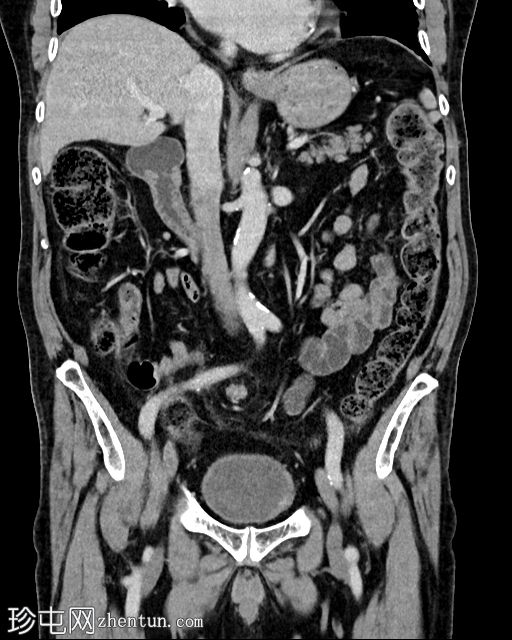

冠状位增强扫描(门静脉期)

乙状结肠系膜呈漩涡征,乙状结肠袢扩张且冗长。乙状结肠和直肠下游塌陷。结肠上游扩张。小肠袢未见扩张。乙状结肠系膜少量积液,脂肪条索状改变。腹膜内未见游离气体。

本病例展现了乙状结肠扭转的典型

影像

学表现,X线片可见“咖啡豆征”,CT可见漩涡征。通过硬式乙状结肠镜检查成功解除了结肠压迫。